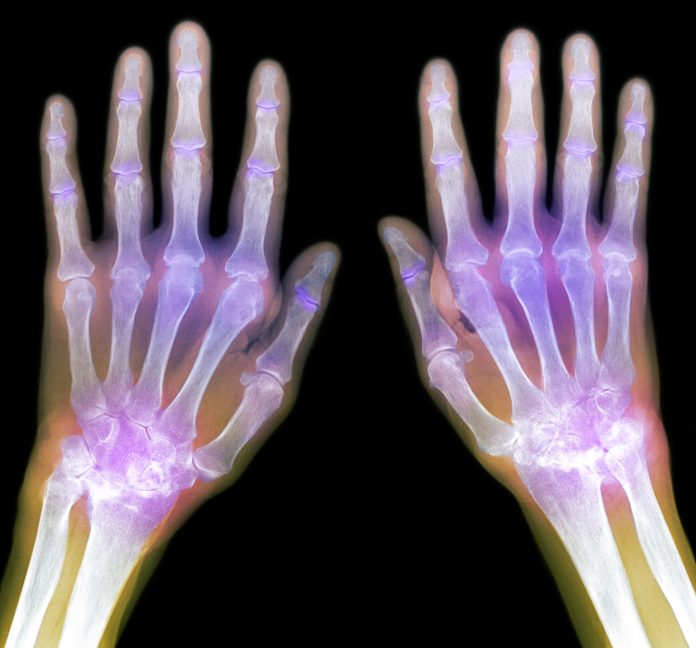

Η οστεοαρθρίτιδα είναι μία από τις πιο συνήθεις παθήσεις που επηρεάζουν τους ηλικιωμένους. Μπορεί να επηρεάσει οποιαδήποτε άρθρωση στο σώμα, αν και οι περισσότεροι άνθρωποι αναφέρουν δυσφορία και πόνο στα γόνατα, τους γοφούς, τη σπονδυλική στήλη και τα δάχτυλα.

Η οστεοαρθρίτιδα εμφανίζεται όταν τα άκρα των οστών σας προστατεύονται λιγότερο με την πάροδο του χρόνου, καθώς ο χόνδρος που τα προστατεύει αρχίζει να φθείρεται.

Όμως όταν ο χόνδρος υποστεί μεγάλη φθορά, τα οστά τρίβονται μεταξύ τους, δημιουργώντας φλεγμονές στην περιοχή και προκαλούν αποκόλληση μικρών κομματιού οστού και χόνδρου.